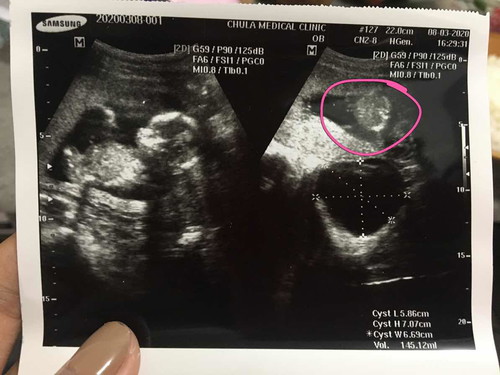

ไปซาวตอน 15w น้องไม่ยอมให้ดู ละมุมนี้ที่หมอปริ้นให้หมอเห็นคนเดียว เราหันไปดูก็ไม่ทันช็อตนี้แล้วหมอบอกว่าอาจจะ ช รอซาวอีกทีรอบหน้า แม่ๆคิดว่า ช อย่างที่หมอบอกมั้ยค่ะ เหมือนที่โผล่มาน่าจะเป็นอย่างอื่นมากกว่าจู๋น้องเลย ส่วนตัวแม่เองอยากได้ ญ มากเลยค่ะ ???

กำลังตั้งครรภ์